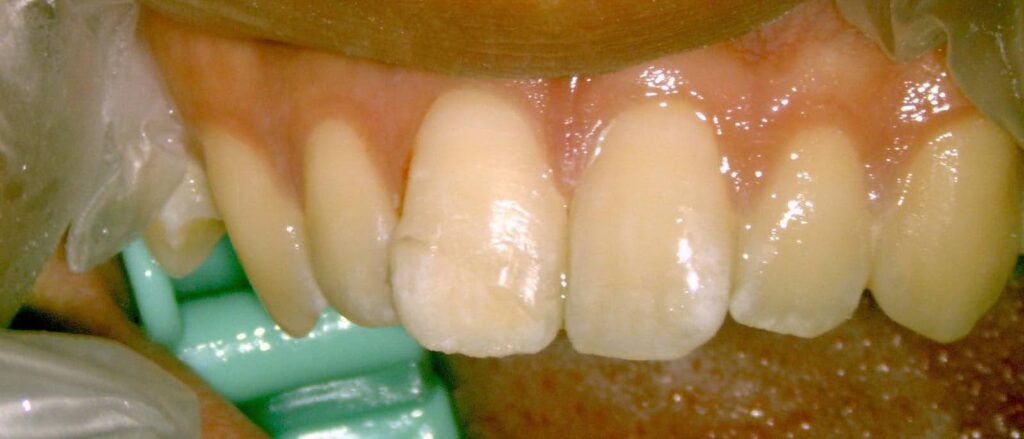

Dr.:麻酔をし、元の位置に引っ張り出して戻し、隣の歯と仮止めします。歯髄(=神経)は傷み残せない状態なので、根管治療をしました。